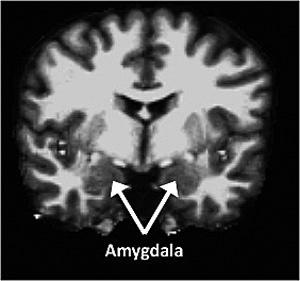

La amígdala, que forma parte de la región

temporal media del cerebro y está relacionada

con el procesamiento de las emociones,

era mayor en los individuos escrupulosos

y menor en los neuróticos.

Fuente: Washington University.

Un equipo de psicólogos de la Washington University en St. Louis, Estados Unidos, ha descubierto que existe una relación entre la personalidad de las personas mayores y el volumen de ciertas áreas de su cerebro, vinculadas a la emoción y al procesamiento de la información social. Un rasgo concreto de la personalidad es la que más afectaría al cerebro: la neurosis, fuente de estrés y de angustia. Según los investigadores, los resultados obtenidos de este estudio, en el que se analizó el cerebro de casi 80 personas, permitirán comprender mejor el origen de ciertas enfermedades, como la demencia o el Alzheimer. La amígdala, que forma parte de la región temporal media del cerebro y está relacionada con el procesamiento de las emociones, era mayor en los individuos escrupulosos y menor en los neuróticos.